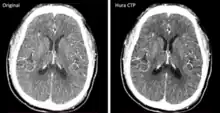

The development and FDA clearance of photon-counting detectors (PCD) for computed tomography (CT) scans in 2022 was an important innovation. These detectors offer a more efficient process for converting X-rays to electrical signals, allowing for better material differentiation and potentially reducing the radiation dose for patients. The image to the right shows two scans of the same brain using old and new CT technology respectively.[24]